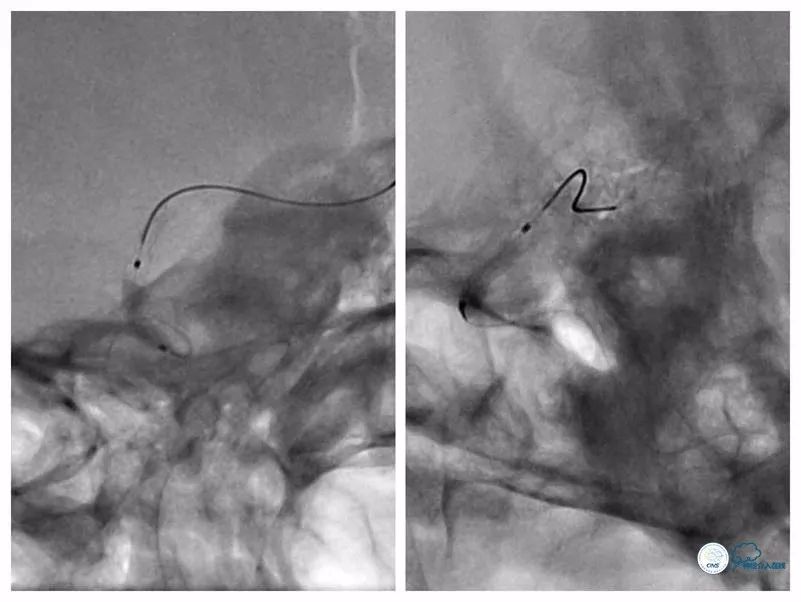

跟进Echelon 10微导管以期通过病变未获成功,遂逐节剪断微导管撤出微导管,保留微导丝。送入Ultra-soft球囊(2.0mm×20mm)至狭窄段近端及远端行球扩后造影显示狭窄程度和前向血流均有所改善(图10)。

图10

沿导丝送入两枚Apollo(2.5mm×8mm)球扩式支架由远及近释放(图11,12)。

图11

图12

其后造影显示支架贴壁可,前向血流TICI 3级(图13)。

图13

本例患者狭窄程度较硬,微导丝通过病变后但微导管无法跟进,由于首过病变的微导丝系200cm短导丝,遂只能采用分节剪短微管方法撤出微导丝(图17)。

图17

此外受限微导丝长度,也不能使用自膨支架。所幸,使用8F导引导管+6F Navien导管,系统支撑性较强,两枚Apollo支架均能到位,才得以顺利完成治疗。术后患者出现眼动脉栓塞症状,予以处理后病情缓解,目前电话随访患者眼部症状消失。